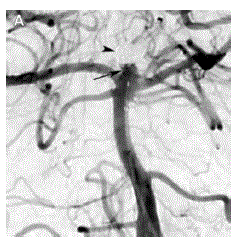

a: sagital T1; b: axial t2 flair; c: axial difusão; d: axial T1 contrastada. e, f, g, h: são as imagens correspondentes às superiores 1 ano após.